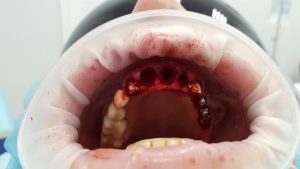

A patient case to the dental clinic with complaint connected with frond teeth defects. After the examination, he decided to provide dental treatment that includes immediate implantation of Alpha Dent implants. During the surgery he has placed 3 Alpha Dent implants in extracted teeth alveolar sockets. Then he placed allomaterial for bone regeneration over implants and sutured the wound.